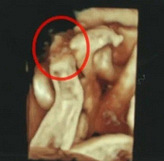

怀孕必买好物推荐来了

有好多妈妈和我一样准备在618的时候“大展拳脚”的?临时抱佛脚,把功课做一做。哪些东西实用、哪些东西鸡肋,心里都一一有数,下面和大家分享一下,怀